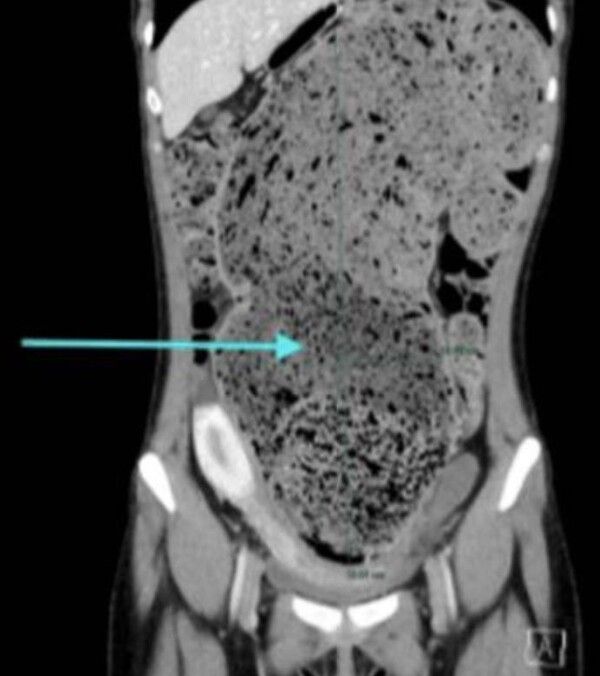

CT 검사 결과 A씨의 대장 말단부인 S상 결장은 15㎝ 이상 비정상적으로 늘어나 꼬여 있었으며 수개월간 축적된 대변으로 가득 차 있었다.